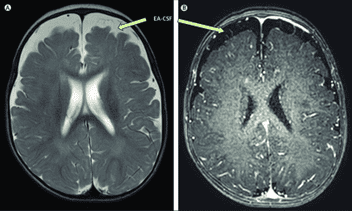

Benign External Hydrocephalus

Benign external hydrocephalus (BEH) is defined by rapid increase in head circumference in infancy, with neuroimaging evidence of enlarged cerebrospinal fluid (CSF) spaces. BEH was postulated to predispose to subdural hematoma, neurocognitive impairments, and autism. Benign external hydrocephalus in infants, characterized by macrocephaly and typical neuroimaging findings, is considered as a self-limiting condition and is therefore rarely treated.

Benign enlargement of the subarachnoid spaces in infancy (BESS or BESSI) also known as benign external hydrocephalus (BEH) is, as per the name, a benign enlargement of the subarachnoid spaces in infants. It usually involves the frontal lobe subarachnoid spaces, and it is characterized clinically by macrocephaly or frontal bossing. The cause is not clear. It has been described as a variation of normal development of the brain, whereby there is a temporary accumulation of cerebrospinal fluid (CSF) in the frontal region.